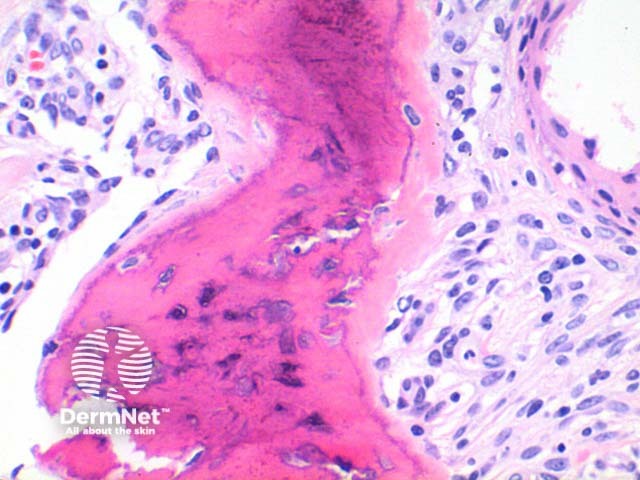

Scanning power of osteoma cutis reveals the presence of dense eosinophilic deposits in the dermis or subcutaneous tissue (Figure 1). Spicules of bone may be seen to perforate the epidermis in the process of transepidermal elimination (Figures 2 and 3). Most cutaneous bone formation occurs by the process of membranous ossification and so associated cartilage tissue is lacking. Bone is identified by osteocytes held within small lacunae (Figures 4 and 5) and the hydroxyapatite eosinophilic support material. In larger deposits, Haversian systems can be seen as concentric osteocytes around a central blood vessel (carried within a Haversian canal).

Figure 3